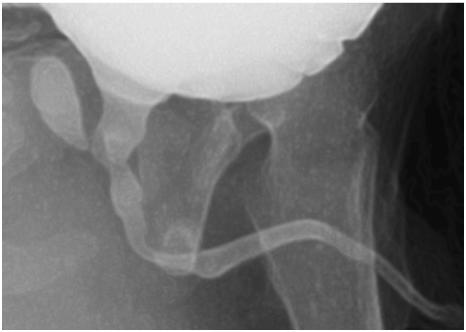

正常的前列腺囊偶尔会在一个常规的VCUG(排泄性膀胱尿道造影)中被附带着发现,可表现为几个毫米的微小憩室,极少数情况下测量可达1厘米以上。大的前列腺囊往往更多地与男性尿道下裂有关。 VCUG和RUG(逆行性尿道造影)确定囊肿的大小,以及它起源于尿道前列腺部。偶尔前列腺囊是分叉状的,反映出它的前体分叉的性质,也就是说配对的苗勒管。大前列腺囊的患者,VCUG期间,会因导尿管优先进入囊肿内而难以直接插入膀胱。使用一种尖端超前的Coude'导管,插尿管时直接按压会阴和/或用手指在直肠内向上压,都会有利于将尿管放置入膀胱。